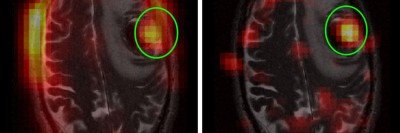

Side-by-side images of brain MRIs.

New Imaging Technique Provides Snapshot of Brain Tumor Activity

A new imaging approach could shorten the time needed to determine whether a brain tumor treatment is working.